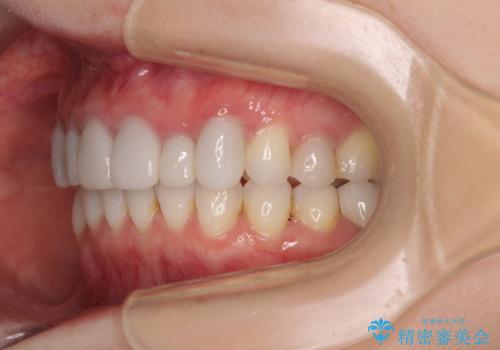

前歯のデコボコと奥歯の咬み合わせをインビザラインで改善

- 上下前歯のデコボコと奥歯の欠損を気にして来院された患者様です。

右下の欠損分は奥歯が倒れ込んでスペースがなくなっていたため、矯正治療により本来の位置に歯を移動させ、オールセラミックブリッジによる欠損補綴治療を行うこととしました。

全顎的にセラミッククラウンが多く装着されているため、インビザラインによる矯正治療を行うこととしました。

右下は移動量が多いため、十分な移動が達成されない場合はワイヤー装置を使用する予定としておりましたが、しっかりとマウスピースを装着してくださったため、前歯とともに十分に歯を動かすことができました。